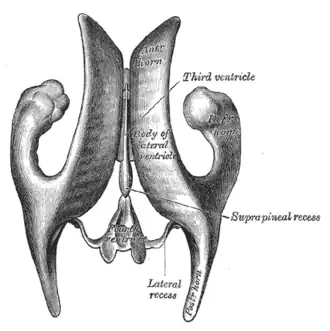

Scheme showing relations of the ventricles to the surface of the brain; oriented facing left. | |

Drawing of a cast of the ventricular cavities, viewed from the side; oriented facing right. | |